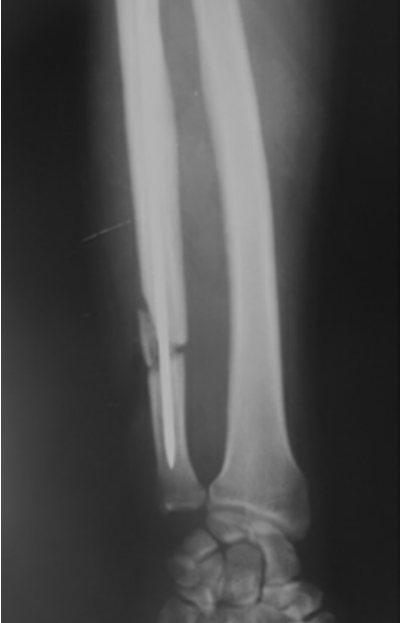

如图7-4-4至图7-4-6即为骨折的影像学检查X线片。

图7-4-4 尺骨骨折当日

图7-4-5 内固定术后

图7-4-6 骨折术后3个月